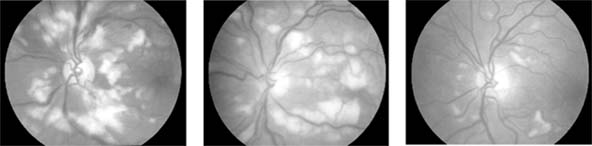

The ocular changes of leukemia occur primarily in those structures with a good blood supply, including the retina, the choroid, and the optic disk (Figure 15-14). Changes are most common in the acute leukemias, where hemorrhages are seen in the nerve fiber and preretinal layers.

Figure 15-14

Figure 15-14: Left: Retinal changes in chronic myeloid leukemia, where dilated veins and hemorrhages may be seen. Right: In acute lymphoblastic leukemia, infiltration of the disk may be seen.

HYPERVISCOSITY SYNDROMES

Increased viscosity results in a reduced flow of blood through the eye. This produces a characteristic dilation of the retinal arteries and veins, hemorrhages, microaneurysms, and areas of capillary closure (Figure 15-15). Polycythemia, either primary or secondary, may produce a hyperviscosity syndrome; the other main causes are macroglobulinemia and multiple myeloma. Reduction of the abnormalities producing hyperviscosity can reverse the retinal changes.

Figure 15-15

Figure 15-15: Hyperviscosity syndrome. Dilated arteries and veins, with hemorrhages and microaneurysms in a patient with hyperviscosity due to elevated IgM levels.